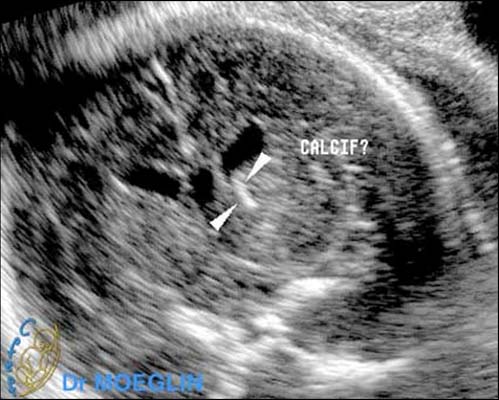

Des calcifications parenchymateuses périventriculaires doivent être recherchées ; celles ci peuvent être isolées. Plus exceptionnellement, une atteinte ischémique peut se traduire par une porencéphalie, une encéphalomalacie multikystique ou une hydranencéphalie.

La séméiologie échographique décrite par les différents auteurs comporte les signes suivants :